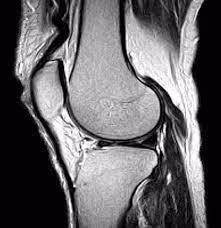

In the realm of chronic injuries, the MRI scan often masquerades as the ultimate truth serum, promising to unveil the hidden challenges within our bodies. However, as someone who spends their entire existence studying the human body, how it moves and the effects various amounts of loading can have on how we move, the reality is far from straightforward. While MRIs are excellent at capturing snapshots of soft tissues (ligaments,tendons, disc, etc) they may not capture the dynamic complexities that impact an athlete's performance.

Athletes are dynamic beings, constantly adapting to the challenges of their sport. An MRI, offering a static snapshot, might not capture the dynamic essence of athletic injuries. Movement, load, and functionality are key components of performance-based physical therapy, and an MRI may fall short in truly grasping the unique demands placed on an athlete's body. I'm often reminded of Family holiday pictures when I think of an MRI...bare with me.